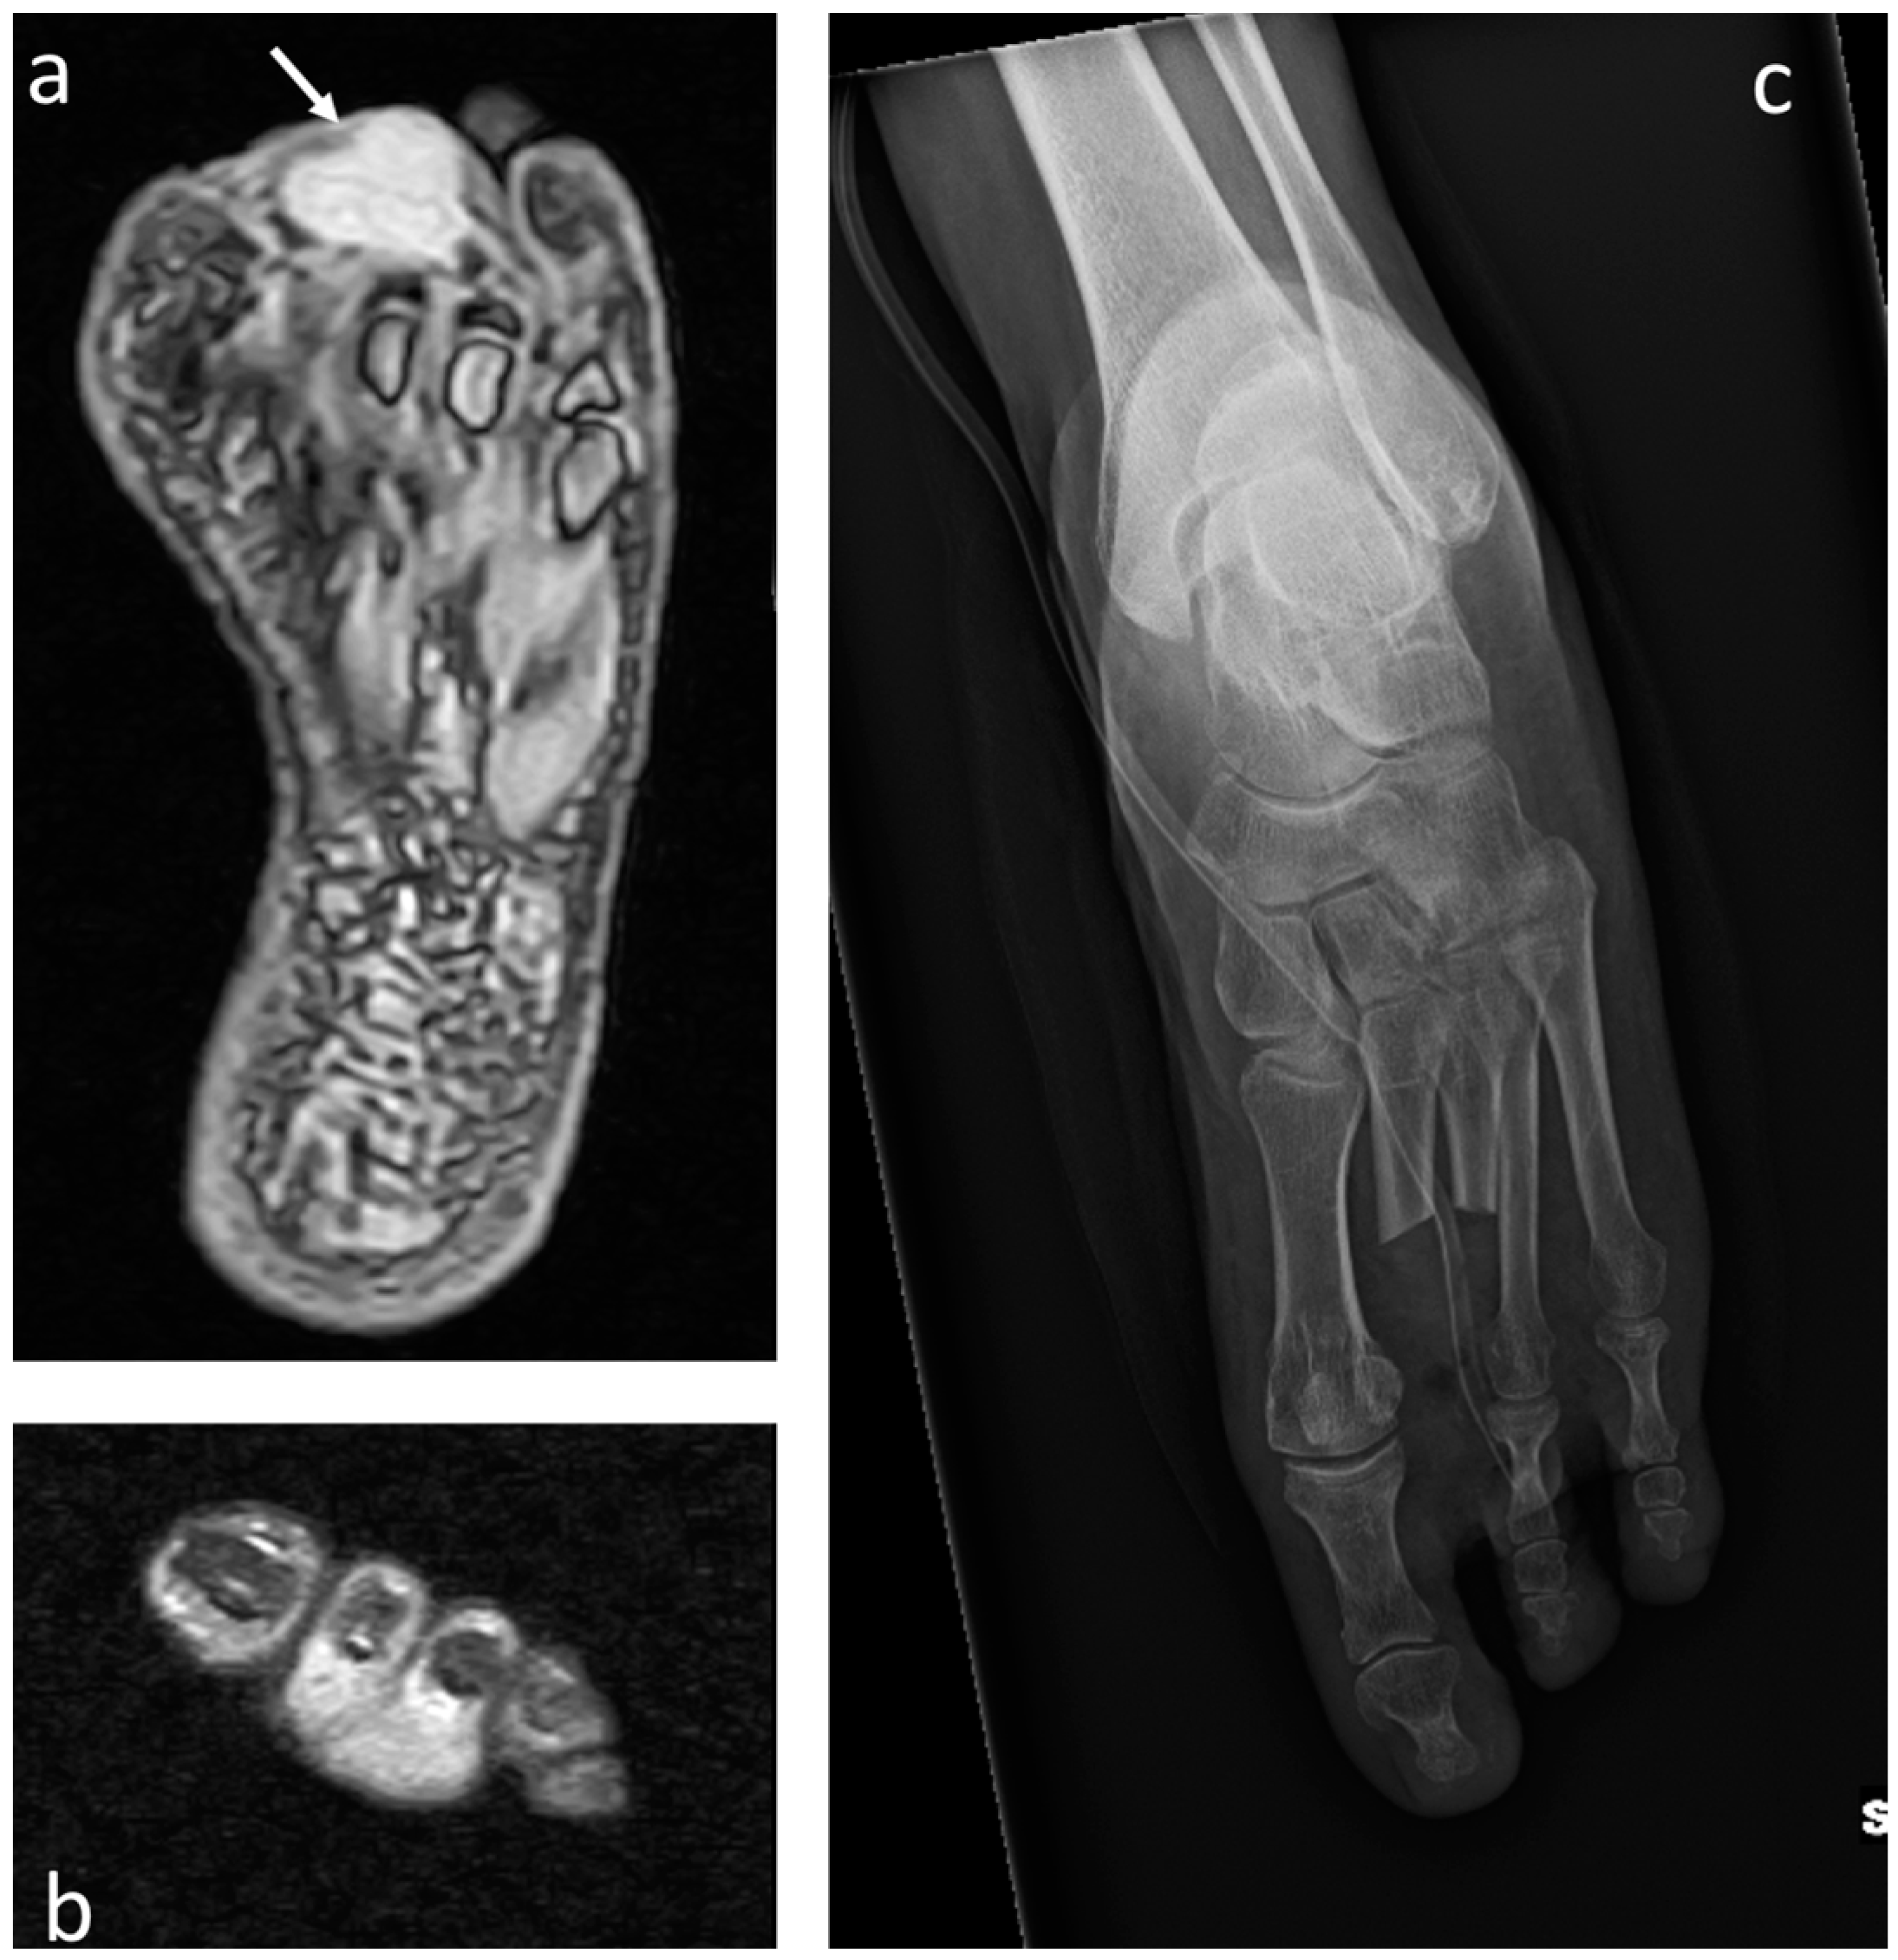

3.1. Osteosarcoma

3.2. Chondrosarcoma

3.3. Ewing Sarcoma

3.4. Acrometastases

4.1. Melanoma

4.2. Epithelioid Sarcoma

4.3. Synovial Sarcoma

4.4. Clear-Cell Sarcoma

4.5. Rhabdomyosarcoma

4.6. Leiomyosarcoma

4.7. Liposarcoma